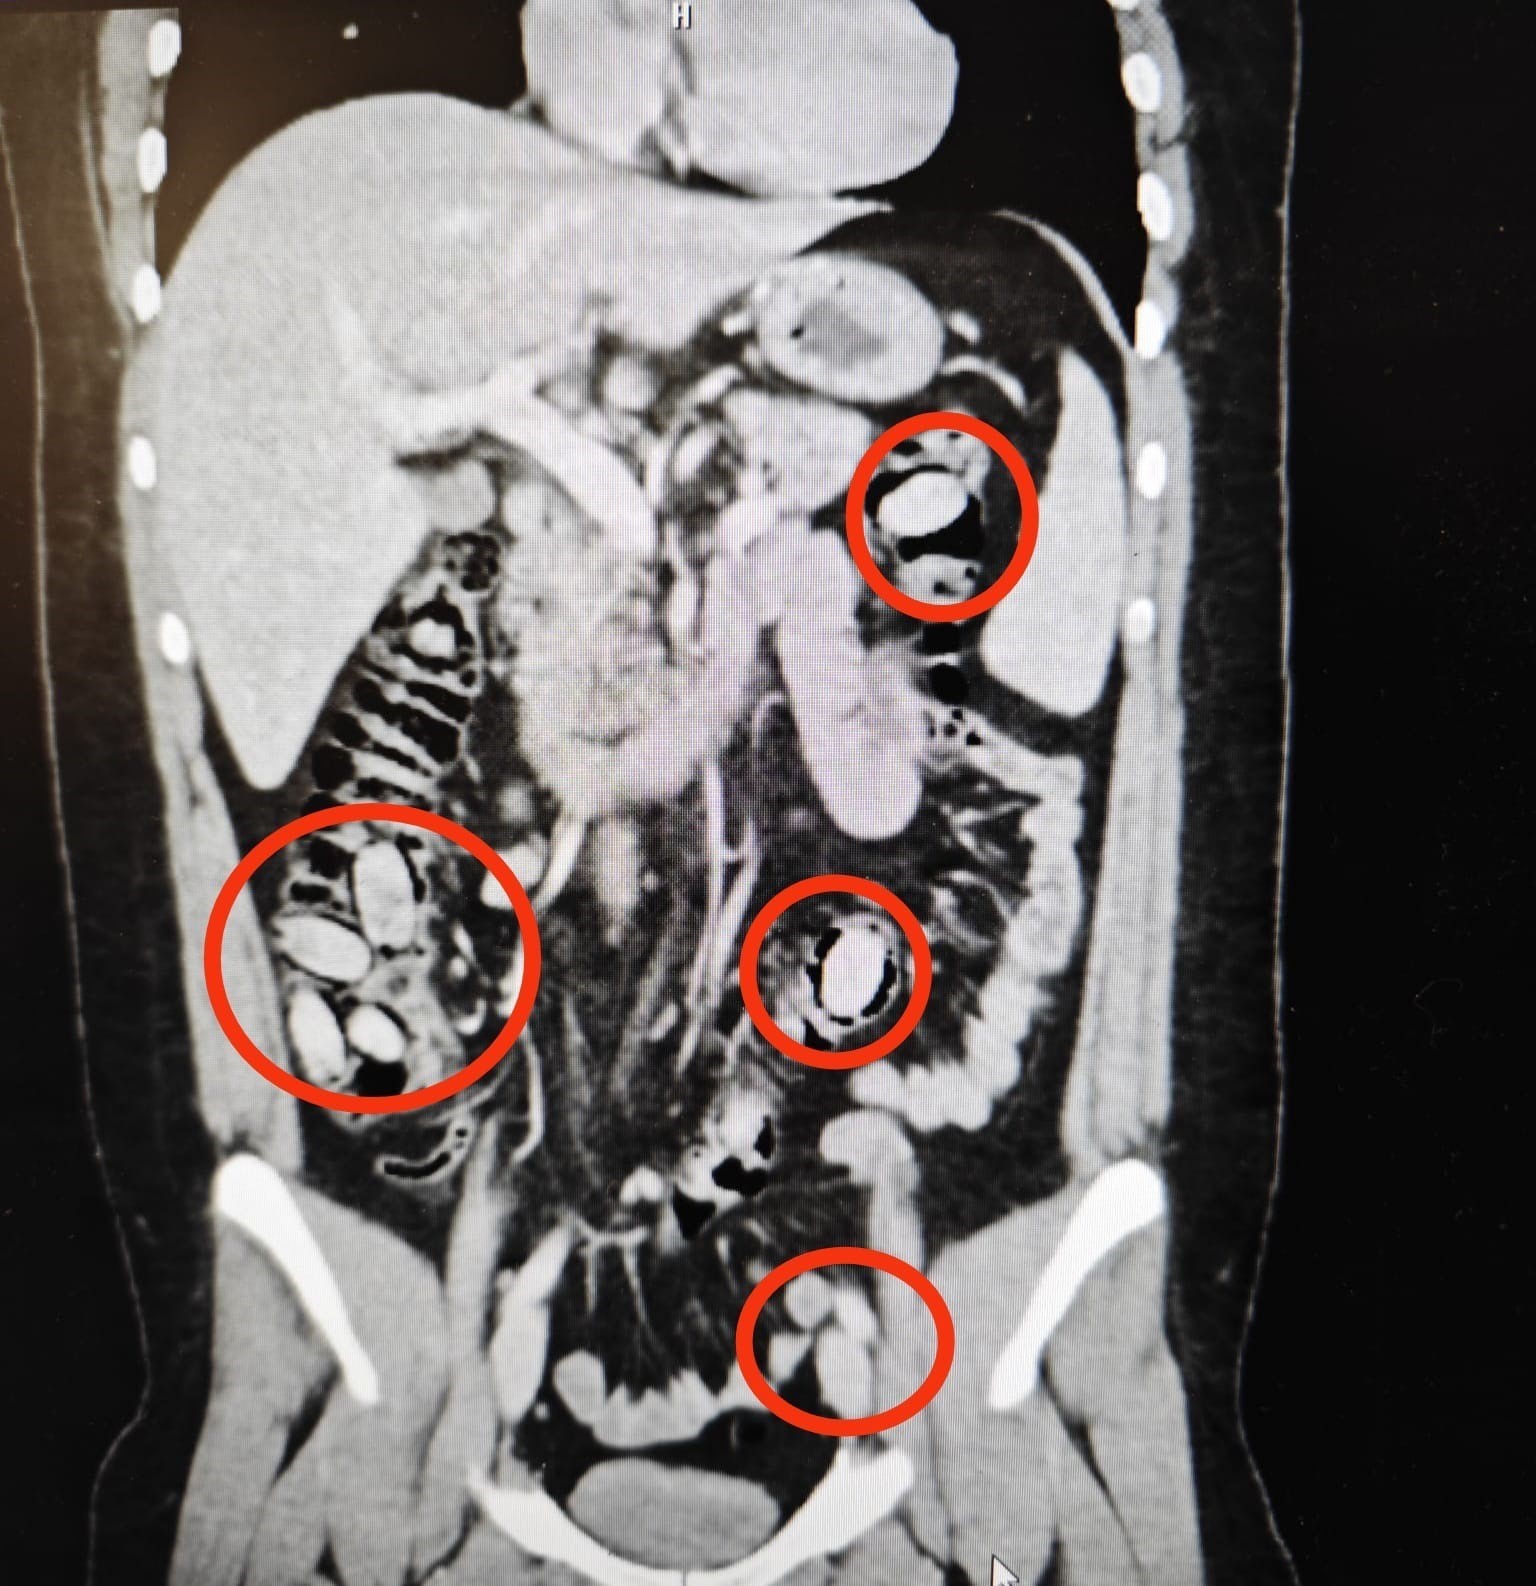

Eskişehir’e 44 kapsül uyuşturucu maddeyi midesinde sokmaya çalışan yabancı uyruklu şahıs polisin dikkati sayesinde yakayı ele verdi. Ameliyatla midesinden uyuşturucu maddeler çıkarılan şahıs çıkarıldığı mahkemece tutuklandı.

Yurtdışından Eskişehir’e gelen S.A. (25) isimli yabancı uyruklu şahsın kent girişindeki çevirme noktasında durumundan şüphelenilmesi üzerine hastanede yapılan detaylı tetkikler neticesinde yutmak suretiyle midesinde 44 kapsül metamfetamin maddesi taşıdığı anlaşıldı. Cerrahi müdahaleyle sözkonusu maddeler şahsın bedeninden çıkarıldı. Tedavisi akabinde şahıs tutuklandı. Yapılan titiz operasyon ile uyuşturucu maddelerin Eskişehir’de piyasaya sürülmeden ele geçirilmesi sağlandı.